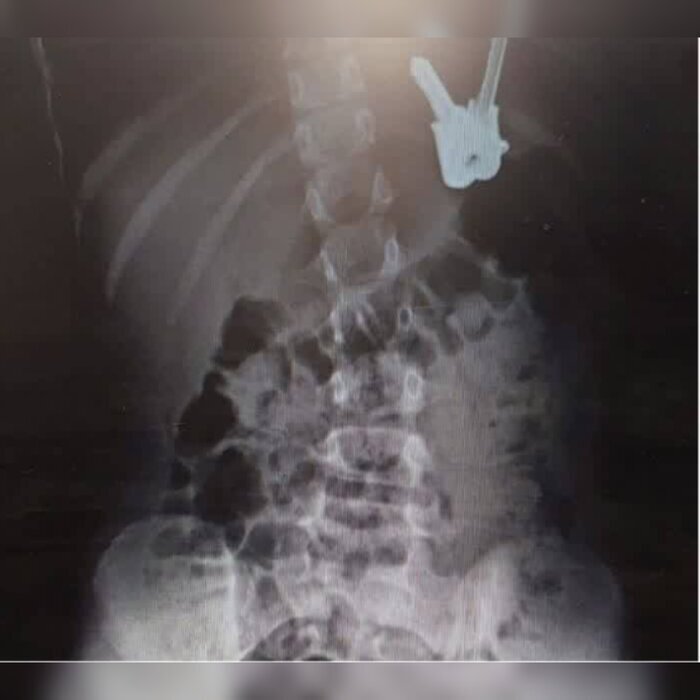

به گزارش شهرآرانیوز، دکتر مهدی جلیلی در این خصوص افزود: این کودک که از درد شکم شکایت داشت، همراه والدین خود به اورژانس این بیمارستان مراجعه کرده بود که احتمال داده میشد دستهکلیدی سهتایی را بلعیده باشد.

وی ادامه داد: بررسیهای نخستین و عکس برداری از شکم، وجود دسته کلید در معده کودک را تایید کرد که با تلاش دکتر الداغی، فوق تخصص گوارش کودکان و گروه آندوسکوپی بیمارستان، دسته کلید با روش آندوسکوپی و تحت بیهوشی، با موفقیت از معده کودک خارج شد.